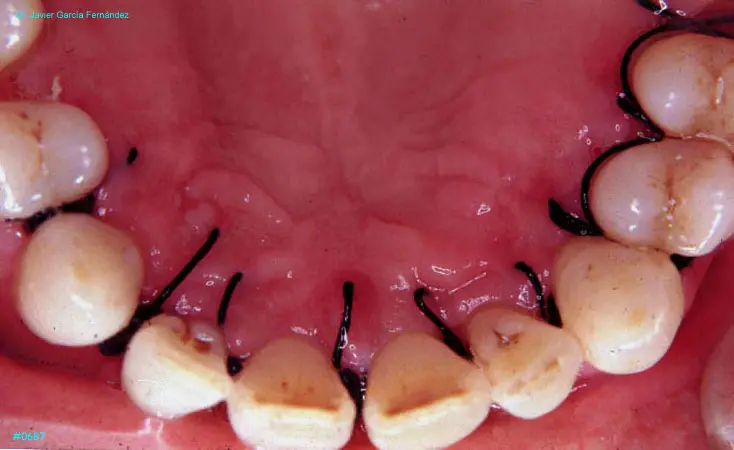

Atlas of Surgical Techniques in Periodontics. Chapter III. Atlas de Técnicas Quirúrgicas en Periodoncia